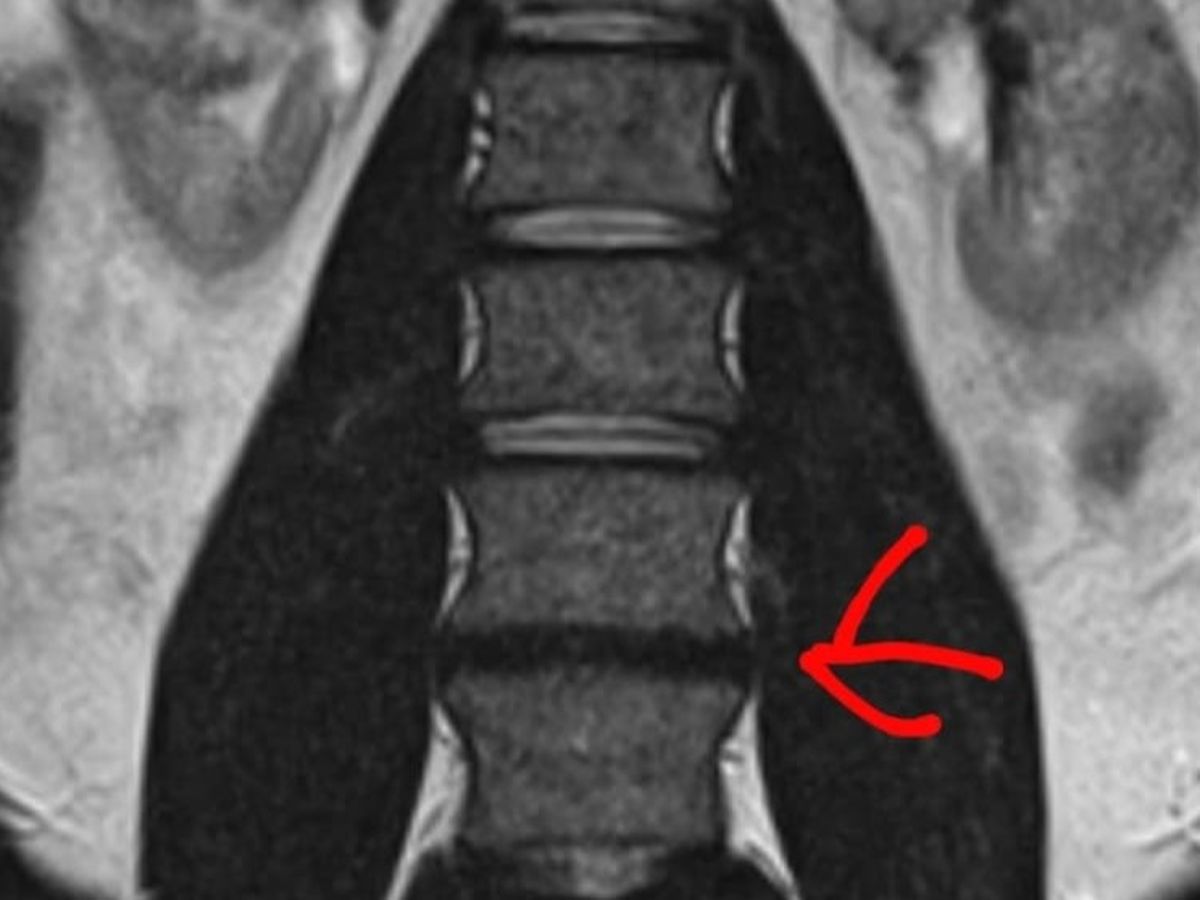

A mis 32 años estoy enfrentando la prueba más dura de mi vida. Tengo un problema severo en los discos L4 y L5 que está afectando a mis nervios y mi movilidad. El dolor es constante, y hoy me impide seguir adelante.